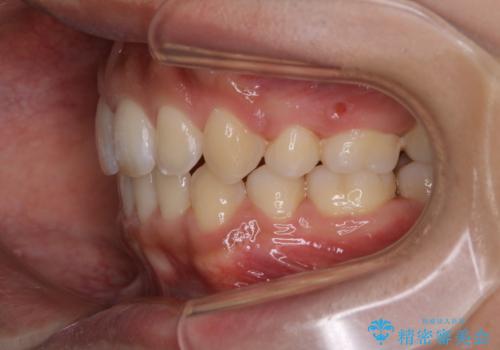

- オーディションで歯並びを指摘されたことから一念発起して矯正治療を行う事にした方です。

親知らずと、前から4番目の歯を抜歯してワイヤー装置による矯正治療を行いました。

人前に出ることが多いため、当初は目立たない装置をご希望されていましたが、歯の移動距離が大きいため効率よく歯を動かせる表側の装置での治療をお勧めしました。すれ違ってしまっていた奥歯もしっかり治すことができました。